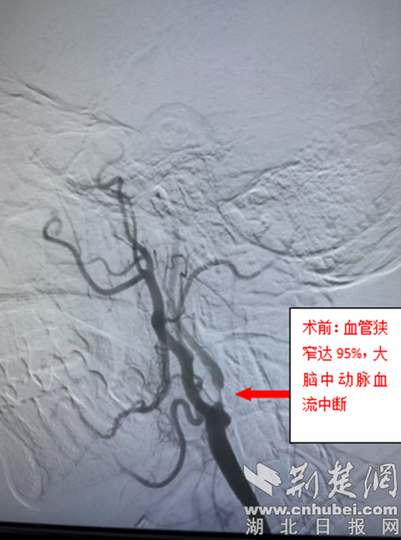

- 中西医结合双镜夹攻巧切“葫芦瘤”

- 十堰市中西医结合医院胸脑外科团队精准介入治疗成功挽救危重患者生命